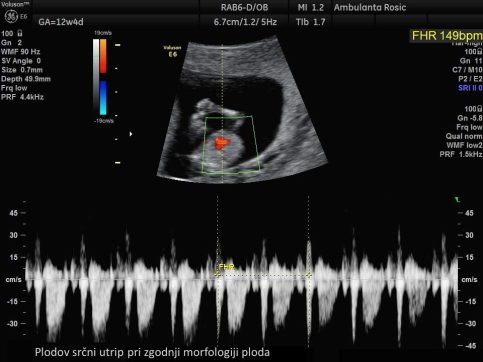

Pri preiskavi z ultrazvokom izmerimo debelino nuhalne svetline na plodovem zatilju. Poleg same meritve debeline nuhalne svetline preiskava zajema tudi meritev velikosti ploda, meritev hitrosti bitja njegovega srca, ugotavljanje prisotnosti nosne kosti in zgodnjo morfologijo ploda, kjer sistematično pregledamo plod in njegov razvoj v prvem trimesečju. Pri izračunu tveganja pa upoštevamo tudi starost nosečnice, saj imajo starejše nosečnice večje tveganje za rojstvo otroka z Downovim sindromom. Širša nuhalna svetlina pomeni večje tveganje za kromosomske nepravilnosti ter druge razvojne nepravilnosti, predvsem srčne napake. Pri velikosti nuhalne svetline nad 3,5 mm je zato svetovan podroben pregled plodovega srca v drugem trimesečju nosečnosti.